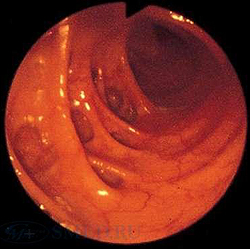

Колоноскопия. Колоноскопию обычно проводят амбулаторно. Она позволяет хорошо визуализировать дивертикулы и любую патологию слизистой. Это диагностический метод выбора в тех случаях, когда больной поступает с ректальным кровотечением или при иригоскопии не удалось хорошо осмотреть толстую кишку.

Однако колоноскопию иногда трудно провести из-за спазма, наблюдающегося при обширной дивертикулярной болезни, а также из-за ригидноcти либо из-за cамих дивертикулов.

Колоноскопия является основным методом диагностики дивертикулита. Данное исследование позволяет провести дифференциальную диагностику заболевания с неспецифическим язвенным колитом, запорами, кишечной непроходимостью и опухолью толстого кишечника. Во время эндоскопии толстого кишечника при дивертикулите обнаруживаются поврежденные устья дивертикулов с воспалением слизистой оболочки вокруг них. Исследование дает возможность уточнить локализацию кровоточащих участков и оценить интенсивность кровотечения.

- Кишечная эндоскопия. Использование эндоскопических методов диагностики (колоноскопия, ректороманоскопия) показано только после купирования признаков воспаления. Колоноскопия является незаменимым методом поиска источника кровотечения, однако может способствовать появлению осложнений заболевания. Преимуществом эндоскопических методик является возможность проведения биопсии, морфологического исследования биоптатов.